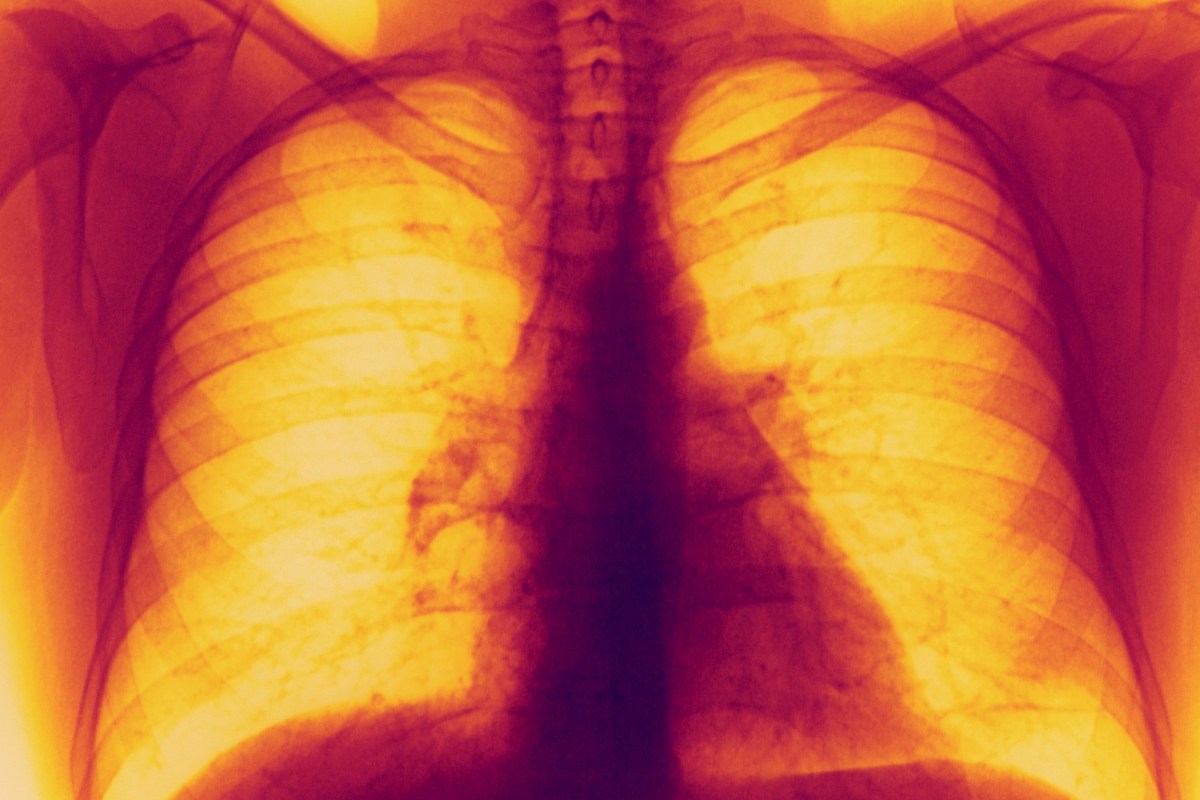

Can A Pill Go In Your Lungs . this article highlights the serious but reversible effects of. a large, moist, sucralfate tablet can completely occlude a bronchus, causing acute respiratory failure. But how does this happen, and what are the signs to look out for? Can a foreign body be aspirated into the lungs? when you aspirate, food, drink, or small objects you've inhaled go into the airway or lungs instead of your stomach. 32 in animal models, sucralfate. An object inhaled into the airways can cause an. pulmonologists must be fully cognizant regarding the urgency of. aspiration pneumonia is an infection of the lungs caused by inhaling saliva, food, liquid, vomit and even small. accidentally swallowing a pill into your lungs, known as aspiration, can lead to serious health complications, such as aspiration pneumonia.